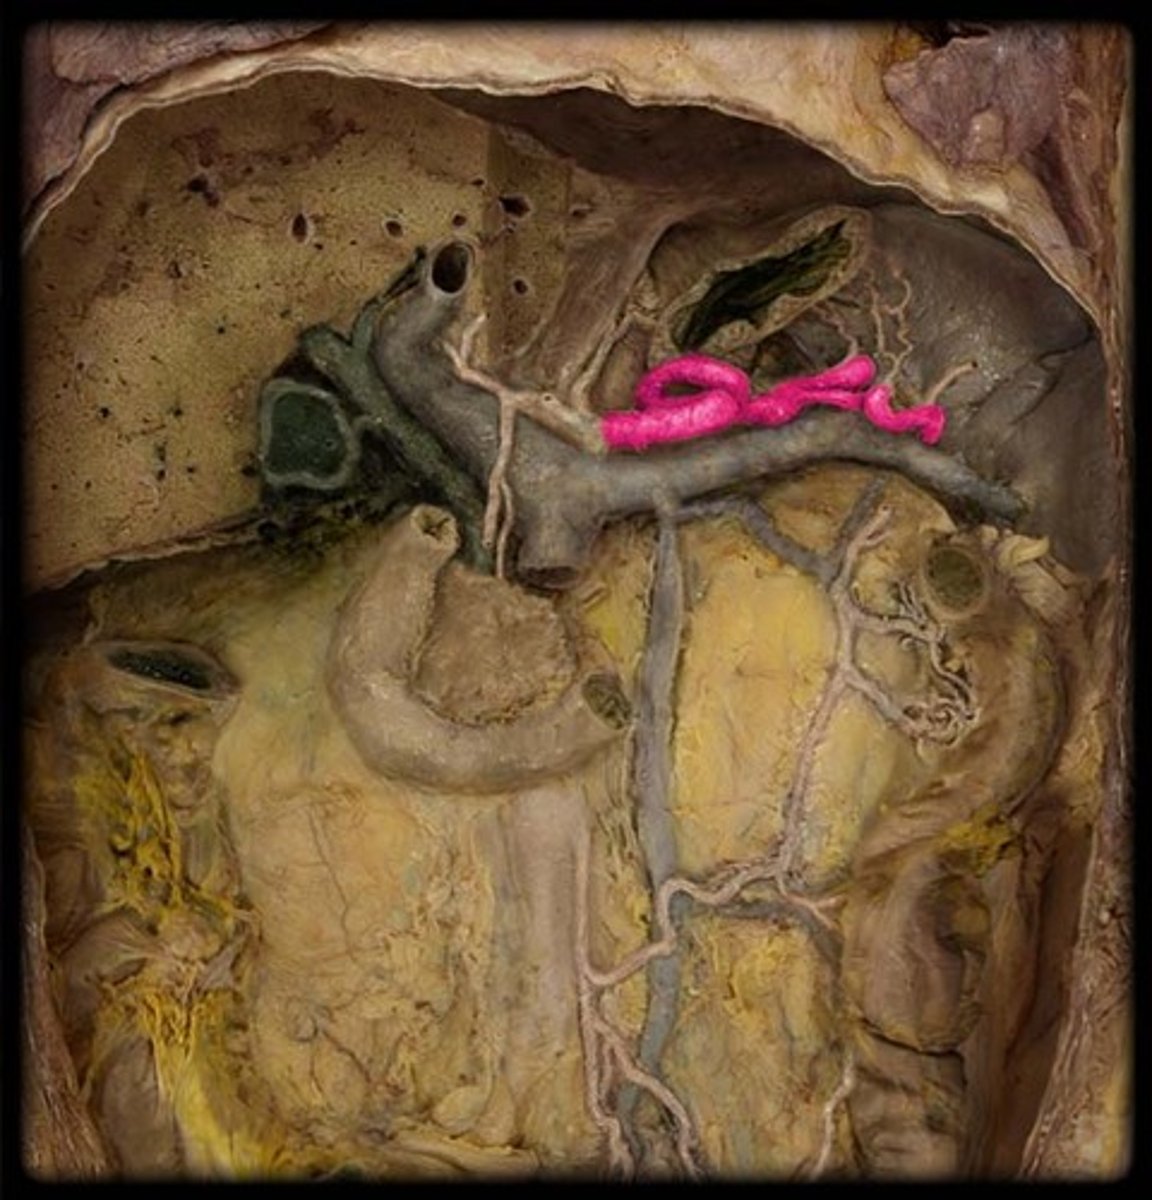

The celiac trunk branches from the...

Abdominal aorta

What are the branches of the celiac trunk?

Left gastric artery

Splenic artery

Common hepatic artery

What are the main two branches off the common hepatic artery?

Proper hepatic artery and gastroduodenal artery

What is this?